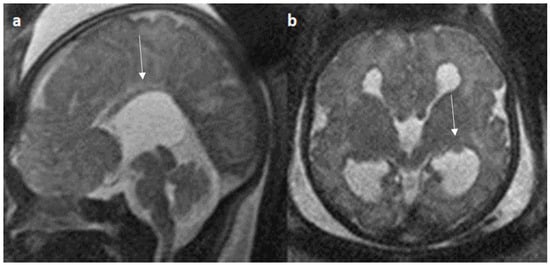

Colpocephaly is seen in 13/24 cases (54%) (Figure 5). Of them, 12 cases had complete agenesis, and one case had hypoplasia. Absent septum pellucidum is seen in 5/24 cases (20.8%) (Figure 6); 4 cases had complete agenesis, and one case had hypoplasia. Probst bundles are identified only in the isolated form of CCA and account for 3/19 cases (15.7%) of complete agenesis and 3/4 cases of the isolated form of CCA (Figure 7). Probst bundles are not seen in other subclasses of CCA. Ventriculomegaly is seen in 7/24 cases with an incidence rate of 0.29%, 5 cases had complete agenesis, and 1 case each had hypoplasia and hypoplasia with dysplasia.

Figure 5.

Fetal MRI images of a 31 gestational weeks aged fetus with complete agenesis of the corpus callosum. (a) A T2-weighted sequence image in sagittal plane shows that the corpus callosum is not visible (white arrow). (b) A T2-weighted sequence image in axial plane shows a “teardrop”-like dilation in the posterior horn of bilateral lateral ventricles suggestive of colpocephaly (white arrow) and absence of corpus callosum and septum pellucidum (red arrow) in the midline. (c) A T2-weighted axial image shows a small interhemispheric fluid collection/cyst in the midline. (arrow). No Probst bundles are observed.

Figure 7.

Fetal MRI images of a 20 gestational weeks aged fetus with complete agenesis of the corpus callosum. (a) A T2-weighted sequence image in axial plane showing non-decussating anterior-posterior white matter tracts known as Probst bundles medial to the lateral ventricles (arrow). (b) A T2- weighted sequence coronal image showing Probst bundles indenting superomedial margins of lateral ventricles. Probst bundles are seen with complete agenesis of the corpus callosum.